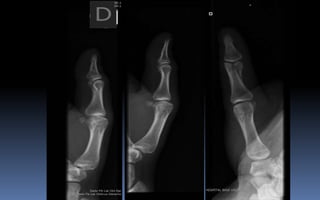

• La radiografía convencional busca representar

un objeto en 3D sobre un plano 2D

• Siempre se deben tomar mínimo 2 proyecciones

AP o PA y Lat.

• Con esto se minimiza el gran problema que tiene

la radiografía convencional:

SUPERPOSICIÓN DE ESTRUCTURAS.